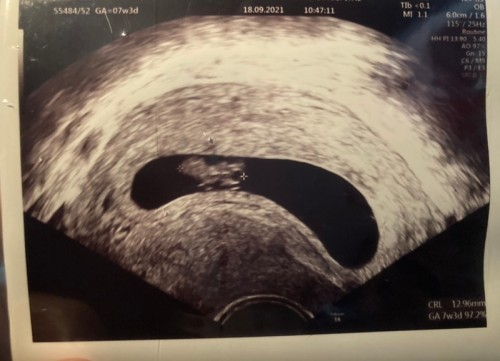

> เมื่อ2 อาทิตย์ก่อน ตั้งแต่รู้ งง มากไม่คิดว่าจะท้อง พอรู้ก็คิดว่า ท้องจริงหรือเนี่ย ไม่มีอาการอะไรเลย แค่ประจำเดือนเลทไป 1 W ตื่นมาลองตรวจฉี่ปรากฎขึ้น 2 ขีด สีจางๆแต่ชัด ขึ้นมาอย่างเร็ว เลยตัดสินใจไปเจาะเลือด ผลออก 4113 mIU ไม่อยากจะเชื่อค่ะ ตั้งแต่รู้ว่าท้องมันทั้ง ดีใจ ตื่นเต้น กังวล ในใจวุ่นวายไปหมด ตั้งแต่รู้ว่าท้อง มีคำถามคือ ท้องจริงหรือ ท้องลมรึป่าว ท้องนอกมดลูกไหม เป็นกังวลในใจจริงๆค่ะ ความกังวลมีอยู่เยอะมาก > จนวันนี้18/9/64 ตัดสินใจไปซาวด์ ดูตัวลูกครั้งแรก 7W3D เพราะทนกับความกังวลหล่าวนั้นไม่ไหวแล้ว หมอบอกแนะนำให้ซาวด์ช่องคลอดเพื่อจะได้ข้อมูลหลายอย่างชัดเจนเลย หมอน่ารักมาก (คือคนเดียวกับที่เราไปเจาะเลือด ด้วยความงงๆ) •••}ตอนหมอซาวด์ ได้เห็นลูก อยู่ในมดลูก เห็นไข่แดง หมอให้ดูหัวใจเขากระพริบ ร้องให้แบบสะอึกเลย พอหมอให้ฟังเสียงหัวใจก็แบบดีใจมาก โล่งอก เราไม่รู้ว่ามีคนเป็นแบบเราไหม แค่อยากแชร์ประสบการณ์ของตัวเอง เผื่อจะเป็นกำลังใจให้ท่านอื่น และคลายกังวลให้ท่านอื่นได้บ้าง เหมือนกับที่เราได้มาอ่านของท่านอื่นๆ และทำให้เราคลายกังวล และยิ้มได้ ในช่วงเวลา2 อาทิตย์ที่ผ่านมา ~การตั้งครรภ์ไม่ง่ายเลยเลย สำหรับผู้หญิงป่วยซึมเศร้าอายุ 35 (ตั้งแต่รู้ว่าตั้งครรภ์ หมอให้หยุดยาไว้ก่อนครรภ์ 3 เดือนไปแล้วค่อยว่ากันใหม่) ที่ต้องกังวลต่ออีกนิดคือ ขอให้ลูกเราสมบูรณ์แข็งแรง จะมาอัพเดทต่อนะคะ วันพฤหัสบดี23/9/64 จะไปฝากครรภ์ หวังว่าข้อมูลจะเป็นประโยชน์ต่อทุกท่านค่ะ เป็นกำลังใจให้ทุกท่านค่ะ✌🏻💐